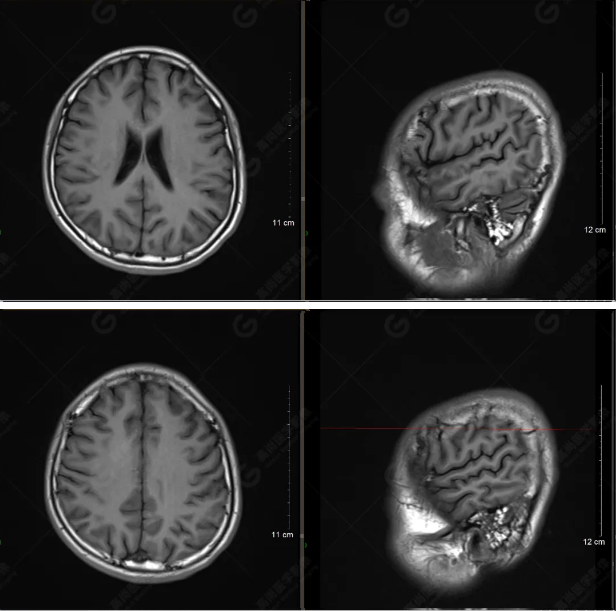

以下是平掃T2WI及FLAIR序列:

以下是T1WI軸位掃描及矢狀位掃描:

雙側(cè)大腦半球?qū)ΨQ,灰白質(zhì)對比正常,顱內(nèi)未見異常信號影。腦室系統(tǒng)未見擴(kuò)大,中線結(jié)構(gòu)居中。腦溝、裂未見增寬。幕下小腦、腦干未見異常。矢狀位示垂體形態(tài)、大小級信號未見異常。所示左側(cè)乳突內(nèi)見多發(fā)短T1長T2信號影。

顱腦MRI平掃未見明顯異常,左側(cè)乳突內(nèi)積血,建議補(bǔ)充SWI檢查。